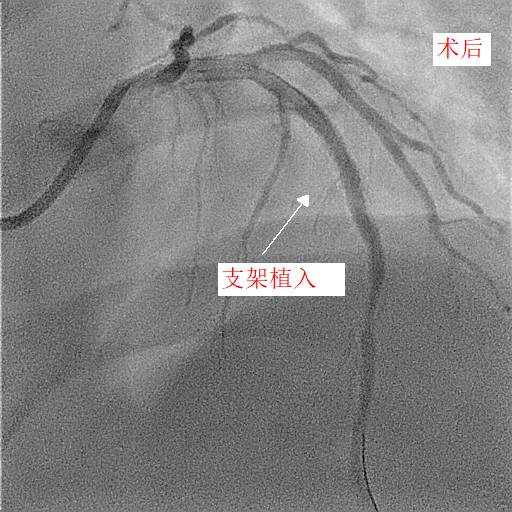

第二天,小天和父亲同一天接受冠脉造影和手术治疗,冠脉造影进一步明确了:小天冠状动脉回旋支完全堵死、前降支90%堵塞,而右冠状动脉也仅有一丝血流通过。造影中医生发现,小天的血管狭窄已经有一段时间,其中的右冠状动脉已经产生了侧支循环。随后医生在患者右冠状动脉里放入了两个支架,恢复了血流。

两天后,医生再次手术解决了左前降支的问题,至于回旋支因为先天血管发育较小,可暂时观察,后续再处理。